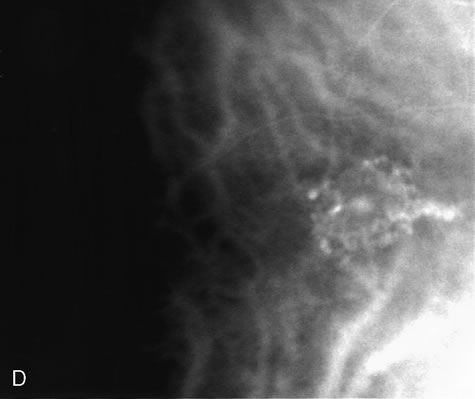

Fig. 9. A. Clinical photograph of the left eye of a patient with exudative neurosensory macular detachment. There were also intraretinal and subretinal hard exudates, subretinal hemorrhage, and retinal pigment epithelium (RPE) changes. B–D. Fluorescein angiography of the same eye demonstrates the presence of stippled hyperfluorescence from the RPE, and late-phase oozing of dye of undefined origin. There was occult choroidal neovascularization.